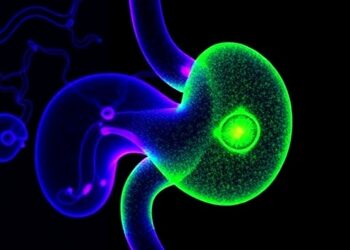

Laser targets pancreatic tumors by homing in on collagen: A breakthrough approach for precision cancer therapy

In a groundbreaking advance that could revolutionize the treatment of pancreatic cancer, researchers have unveiled a precision laser technique that ...